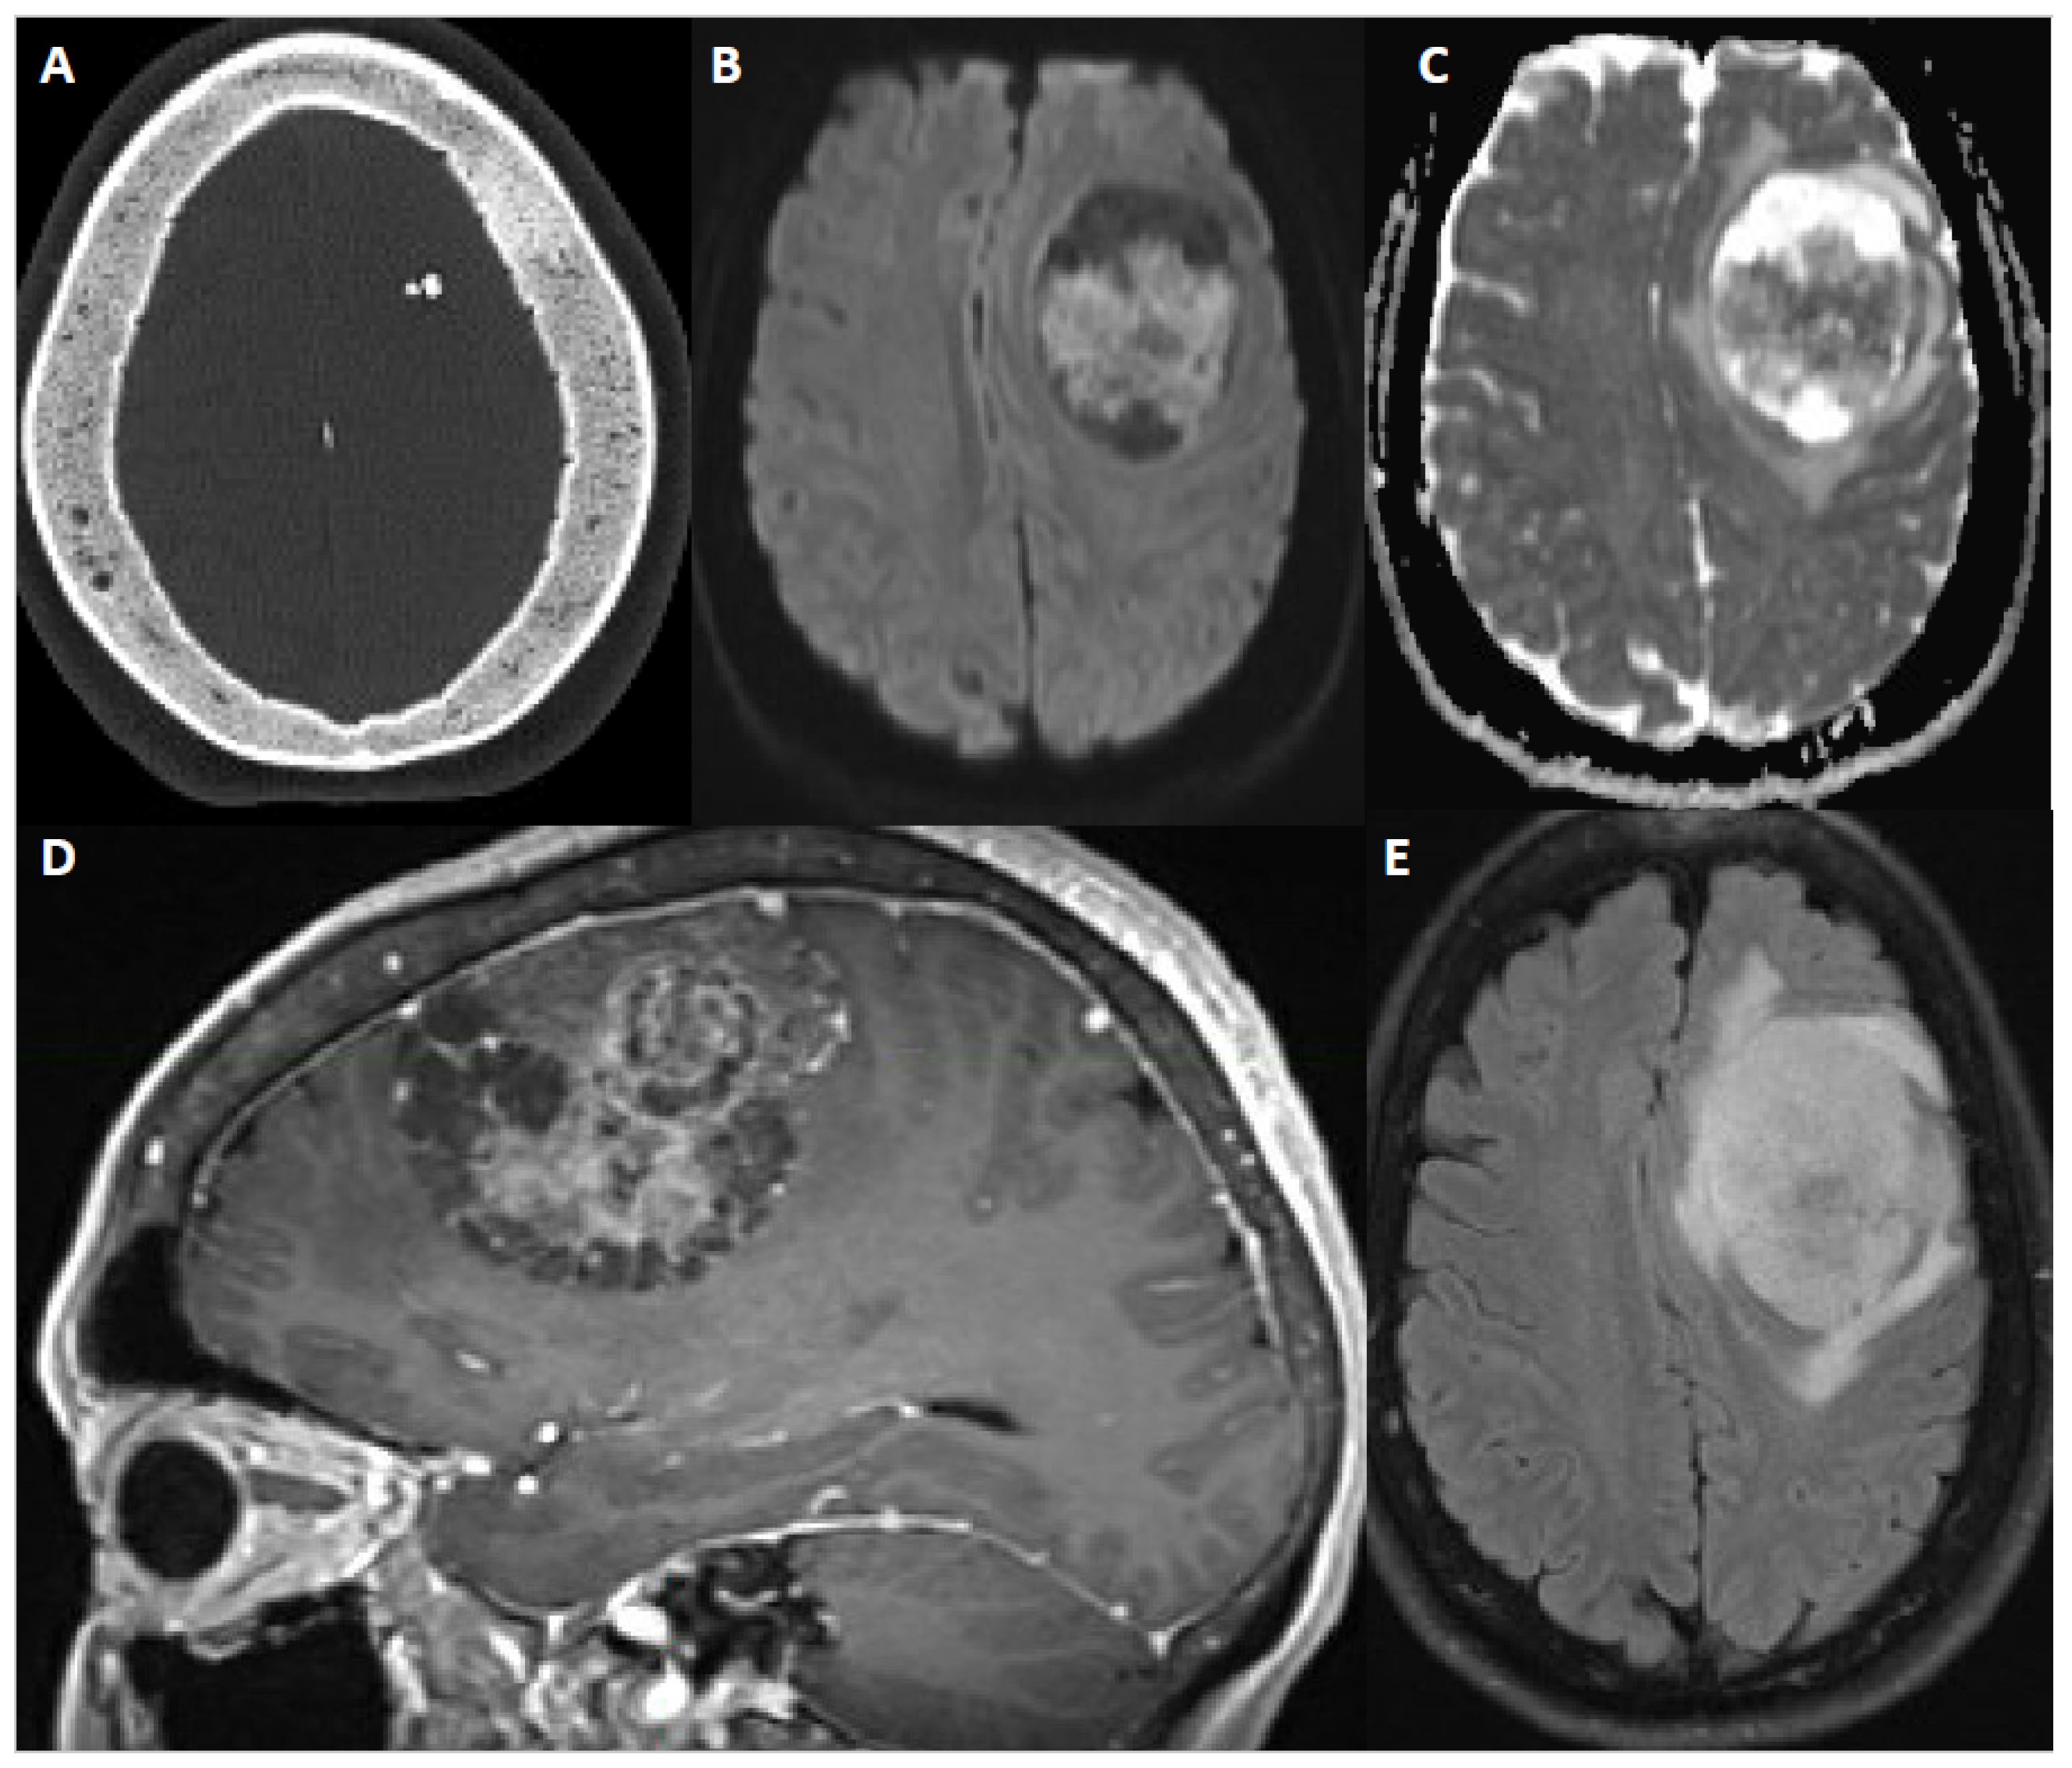

6. Imaging

- Magill, S.T.; Nguyen, M.P.; Aghi, M.K.; Theodosopoulos, P.V.; Villanueva-Meyer, J.E.; McDermott, M.W. Postoperative Diffusion-Weighted Imaging and Neurological Outcome after Convexity Meningioma Resection. J. Neurosurg. 2021, 135, 1008–1015. [Google Scholar] [CrossRef] [PubMed]

- Villanueva-Meyer, J.E. Modern Day Imaging of Meningiomas. In Handbook of Clinical Neurology; Elsevier: Amsterdam, The Netherlands, 2020; Volume 169, pp. 177–191. [Google Scholar]

- Joo, L.; Park, J.E.; Park, S.Y.; Nam, S.J.; Kim, Y.-H.; Kim, J.H.; Kim, H.S. Extensive Peritumoral Edema and Brain-to-Tumor Interface MRI Features Enable Prediction of Brain Invasion in Meningioma: Development and Validation. Neuro-Oncology 2021, 23, 324–333. [Google Scholar] [CrossRef]